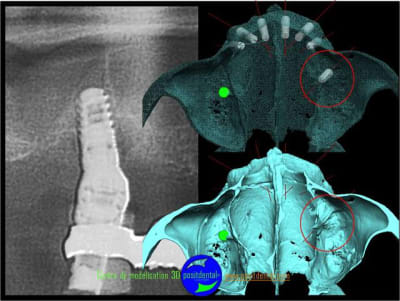

votre avis sur ce cas clinique

suite

Pose d’un implant au maxillaire dans une zone de faible densité

précision de la chirurgie guidée condensée

Le guide chirurgical, positionneur d’implants reste en place jusqu’à la pose des implants.